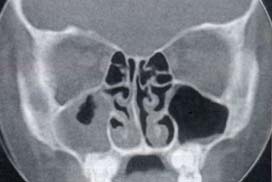

El análisis reveló que al tomar una tomografía computarizada de dichos casos quedaba en evidencia la desviación de la lámina perpendicular del Etmoides, la cual es propiciada per se (Figura 1), sin otras alteraciones, o es inclinada lateralmente por un cornete medio patológico, bien por estar neumatizado, (concha bullosa) (figura 2), por el tipo de inserción de este en el receso frontal, por una curvatura paradójica (figura 3), por su hipertrofia o hiperplasia, o que éste a su vez esté medializado por una bulla etmoidal prominente, figura 4 y/o una hipertrofia de la apófisis unciforme.

| Figura 1.En tomografía computarizada se observa una desviación de la lámina perpendicular del etmoides sin otros desencadenantes. | Figura 2.Tomografía mostrando una desviación etmoidal por una concha bullosa. |

![]() |

| Figura 3.Tomografía con desviación septal por un cornete medio paradójico. | Figura 4.Tomografía con celdilla Aggeriana gigante desviando la lámina perpendicular. |